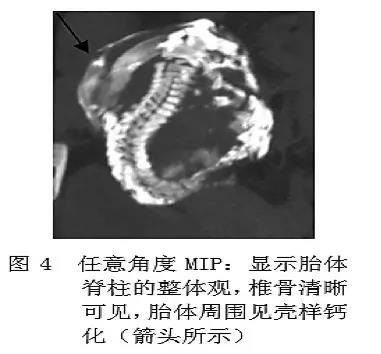

石胎的主要诊断手段是影像学检查,包括 B 超,X 线和 CT 等。超声下可见高回声光团和胎儿结构回声,X 线可以看到胎头、脊柱、肋骨及四肢等结构,CT 表现可见钙化的胎膜和胎儿(见下图)。

石胎 CT 图像

(图片来源:邓小强. 腹腔石胎 1 例. 中国医学影像技术 2010, 26( 11))

鉴别诊断有难度时,可以考虑进行多层螺旋 CT(MSCT)扫描,更能直观、多方位、多角度地显示脊柱、肋骨、四肢及胎膜钙化情况,为临床提供准确的影像信息(见下图)。

图片来源:吴德红等. MSCT 对腹腔石胎的诊断价值. CT 理论与应用研究, 2015, 24(1): 129-134.